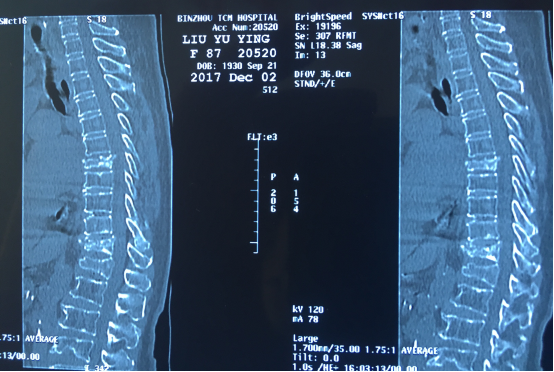

87岁的患者刘女士因腰背部疼痛剧烈,翻身活动困难而入院。入院前,刘女士及其家人四处求医问药,于外院诊断为陈旧性的腰椎椎体压缩骨折,由于患者年龄较大、手术风险较高,嘱其卧床休息,未给予特殊处理。入院后,刘维克主任对患者进行了详尽的检查,发现病位是胸椎7、10节段的新发椎体压缩骨折,如不进行手术干预,患者将遭受更长时间的痛苦。我院脊柱外科考虑该患者已87岁高龄,既往患有高血压、支气管炎、肺栓塞、心房颤动等基础疾病较多,刘维克主任及其团队经过反复论证,为患者设计了微创而高效的手术方案。

术 前